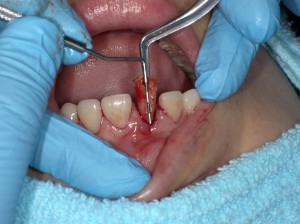

根尖病巣あっても廷出問題なくできます。こんな感じ

PBN1813_160815172523(調整後)骨縁下で破折。病巣も大きい

ZB1813_160822160844PICT0301(調整後)一番歯質が無い所でも9~10mmあります